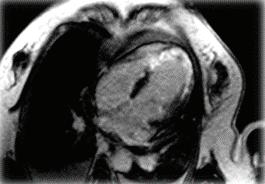

Контролната конвенционална ангиография показа частична реканализация на М2-М3 сегмент TICI II А (Фиг. 2 и 3).

Фиг. 1 Фиг. 2 Фиг. 3